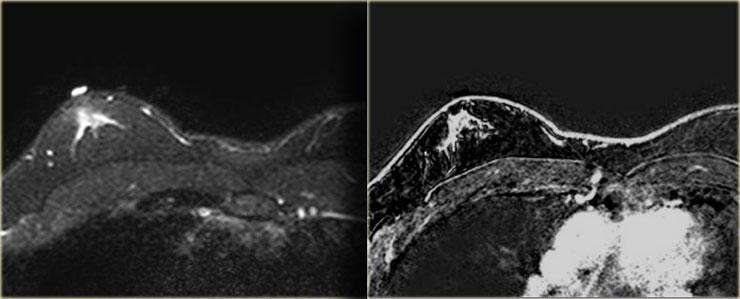

Bên trái là hình ảnh chuỗi xung T2W có xóa mỡ và chuỗi xung T1W sau tiêm thuốc tương phản từ Gadolinium có xóa mỡ.

Một bác sĩ chẩn đoán hình ảnh không quen đọc nhũ ảnh nam giới đã chỉ định MRI để giải quyết vấn đề.

Rõ ràng MRI này được thực hiện vì lý do không phù hợp.

MRI không nên được sử dụng để giải quyết một vấn đề có thể được giải quyết bằng nhũ ảnh.

Dù sao, MRI cũng cho thấy hình ảnh gynecomastia thể nốt.